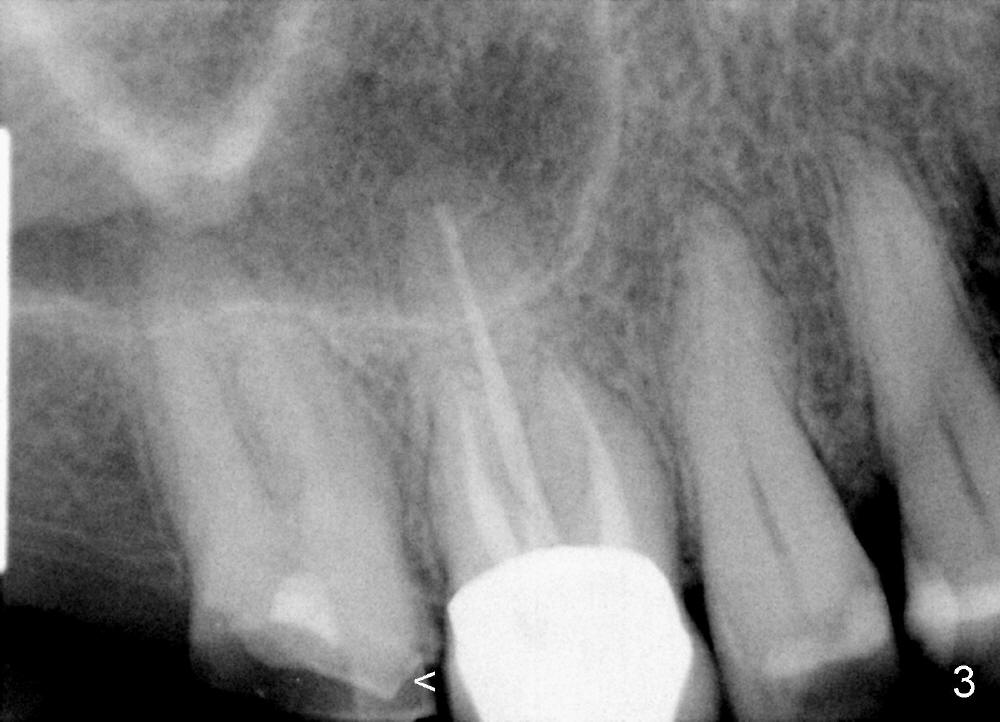

A 51-year-old lady has multiple restorations (Fig.1-3), e.g., amalgam (A in Fig.1) of the upper right 2nd molar as well as history of pulpotomy. The 1st molar has periapical radiolucency (* in Fig.1) and needs root canal therapy. The lower 3rd molar occludes (Fig.2 arrow) with the upper 2nd molar. The latter fractures subgingivally (Fig.3 <) and is extracted with a large MB root (Fig.4) and MB socket (Fig.5). The gingival one third of the palatal wall is defective, as indirectly indicated by granulation tissue palatally (Fig.5 <). So the osteotomy for the immediate implant will not be placed in the palatal socket. The septum is pointed coronally. The pointed portion of the septum is removed; initial osteotomy is formed by 1.5 mm pilot drill in the septum, followed by 2-5 mm osteotomes with the depth of 17 mm. The enlarging osteotomy is deviating buccally; drills are being used to move the osteoomy palatally without much success. When a 5 mm tap is inserted, it is stable and appears to be inside the maxillary sinus (Fig.6). In fact the osteotomy has bony walls around (Fig.7 <), including apical, when the tap is removed. Preop PA shows that the palatal root is apical to the sinus floor (Fig.1 between arrows).